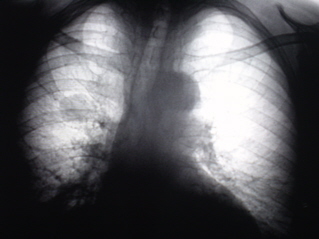

Рентгенологическое исследование проведено по стандартной методике (на РДК на 3 рабочих места – «Вироматик»).

3.Рентгенограмма правого лёгкого.

Иллюстрация 3 и 4 – фрагменты рентгенограмм – правая половина грудной полости и фрагмент с увеличением – фокусная тень на уровне 2 ребра неоднородной структуры.